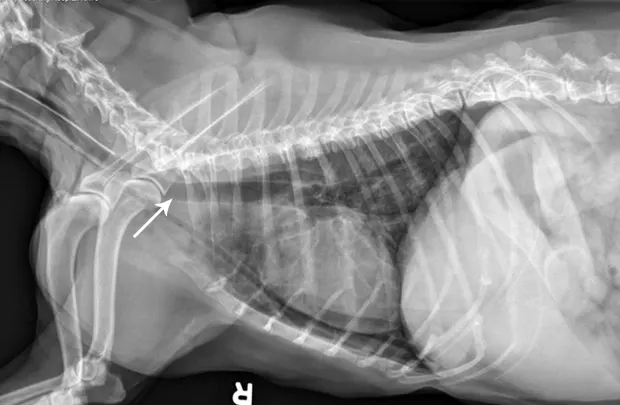

Replacement of a blocked esophagostomy tube attempted with an awake patient resulted in collapse of the stoma, inadvertent placement of the tube (arrow) into the mediastinum, and subsequent mild pneumothorax.